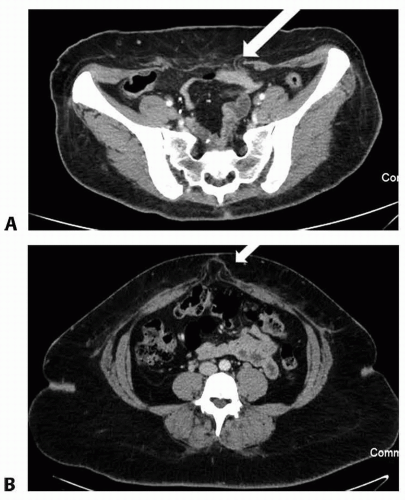

Routine imaging is not necessary in the presence of an adequate physical exam, but CT should be obtained in the case of hernia (FIG 2).

CT scans are obtained if there is clinical concern for hernia. If a hernia is present, a combined hernia repair and panniculectomy is planned.